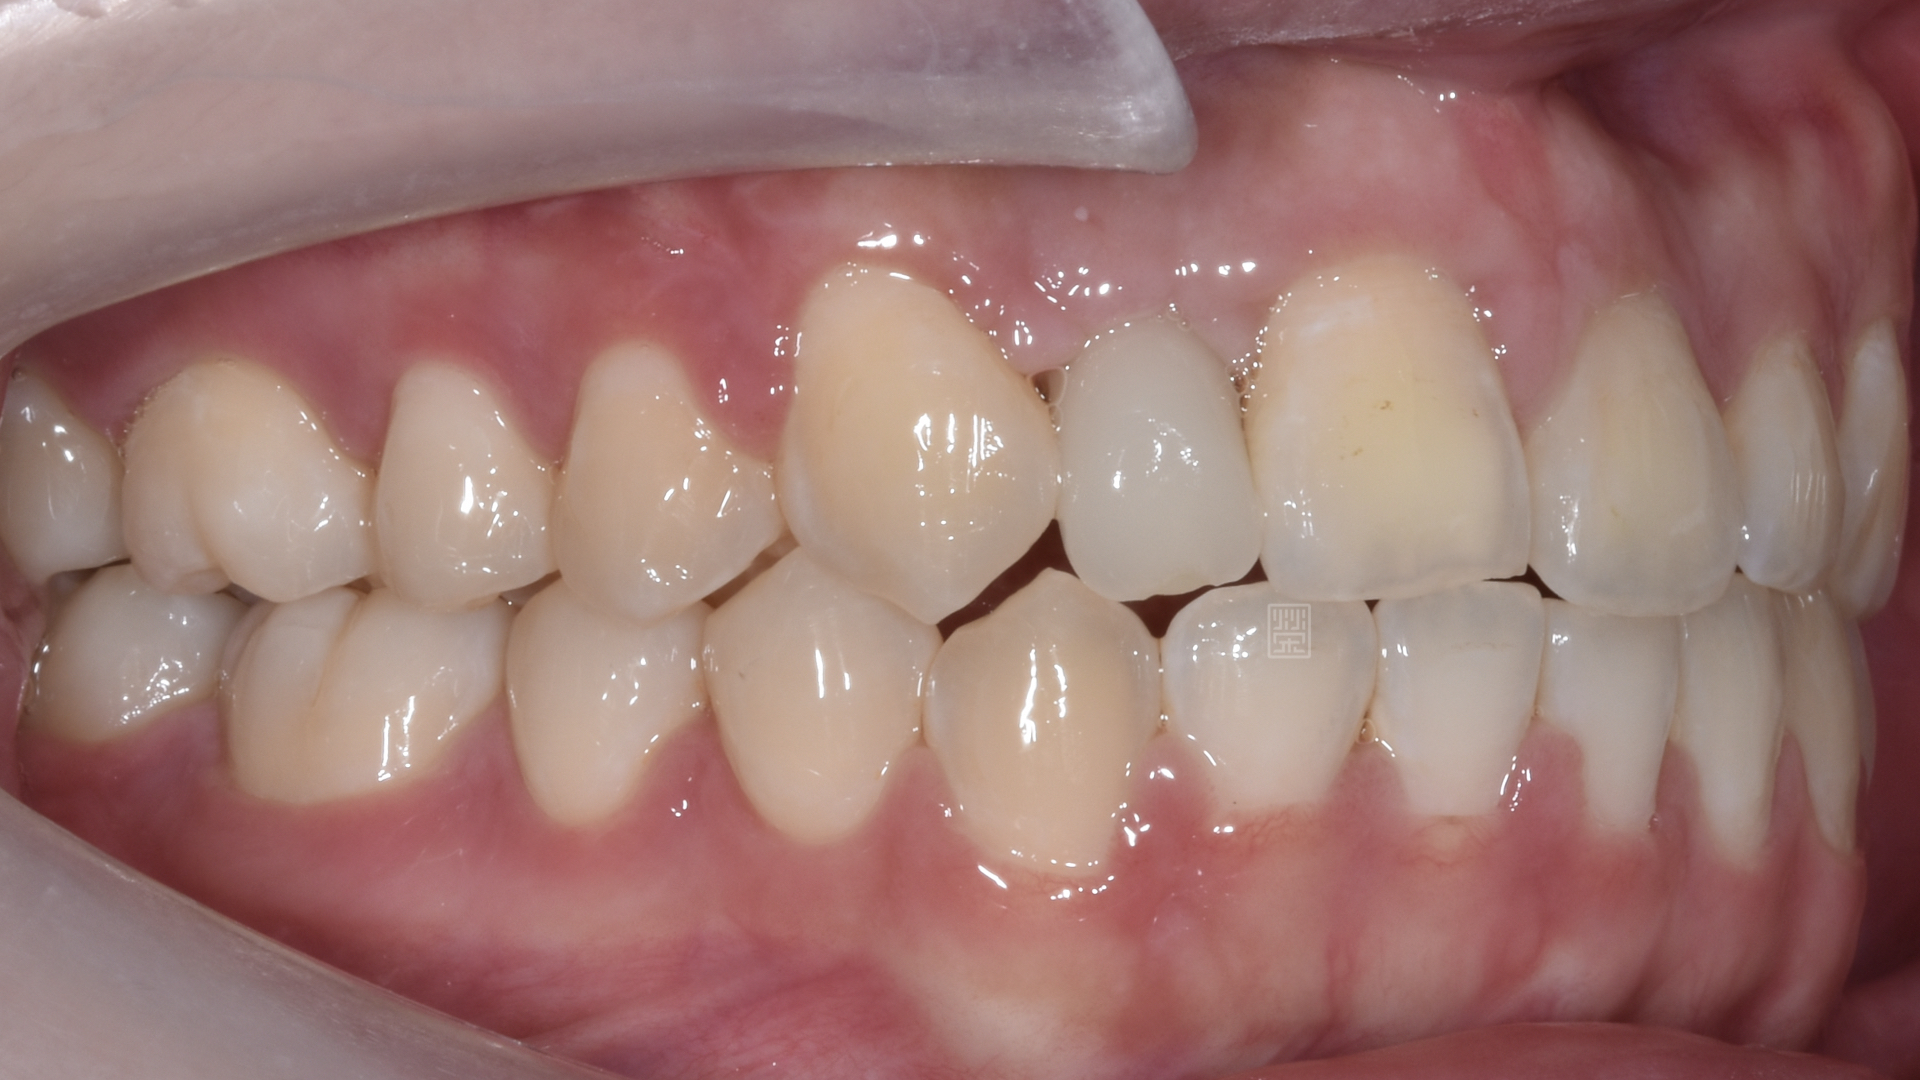

治療前牙齒因車禍有縫且缺牙

長期缺牙側門牙空間不足